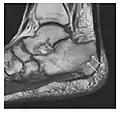

The greater tuberosity of the humerus is also an illustrative location of occult fractures. The osseous injury may follow seizures, glenohumeral dislocation, forced abduction, or direct impaction. They are commonly discovered on MRI in symptomatic patients with suspicion of rotator cuff tear. Coronal images are best suited for detection. They appear as crescentic oblique lines surrounded by a bone marrow edema pattern (Figure 5). The rotator cuff must be inspected since associated ligamentous lesions are common. In the ankle, malleoli and tarsal bones should be checked carefully for any cortical disruptions and radiolucent lines that may reveal a fracture. Awareness of the exact location of the pain will help direct the attention of the interpreter when searching for very subtle signs of fracture (Figure 6).[1]

Figure 6: Subtle anterior talar fracture in a 39-year-old man presenting with ankle pain after a fall. (a) Anteroposterior radiograph shows a subtle oblique radiolucent line through the talus (white arrows). (b) Sagittal CT reformation confirms the presence of an anterior talar fracture with cortical offset (black arrow). Avulsion fractures, which consist of a detached bone fragment resulting from a ligament or tendon pulling away from the bone, may also present with subtle radiographic signs. Tiny osseous fragments near the presumed attachment site of a ligament suggest this diagnosis. Common sites are the lateral tibial plateau (the Segond fracture), the spinal tuberosity of the tibia resulting from anterior cruciate ligament avulsion, and the ischial tuberosity.[1]

a

b